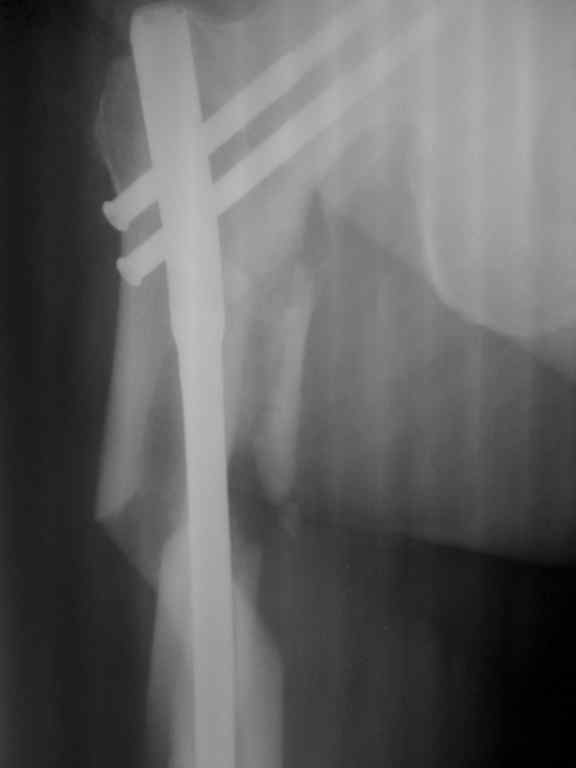

Re: Несросшийся перелом бедра.Выбор операции?

Р-гр после операции